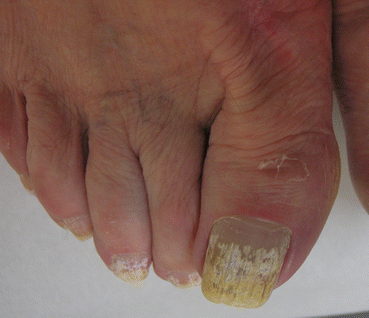

Fig. 4.7

SWO yellowish desquamating patch

Fig. 4.8

SWO: note the yellow-white discoloration and crumbling of the nail surface